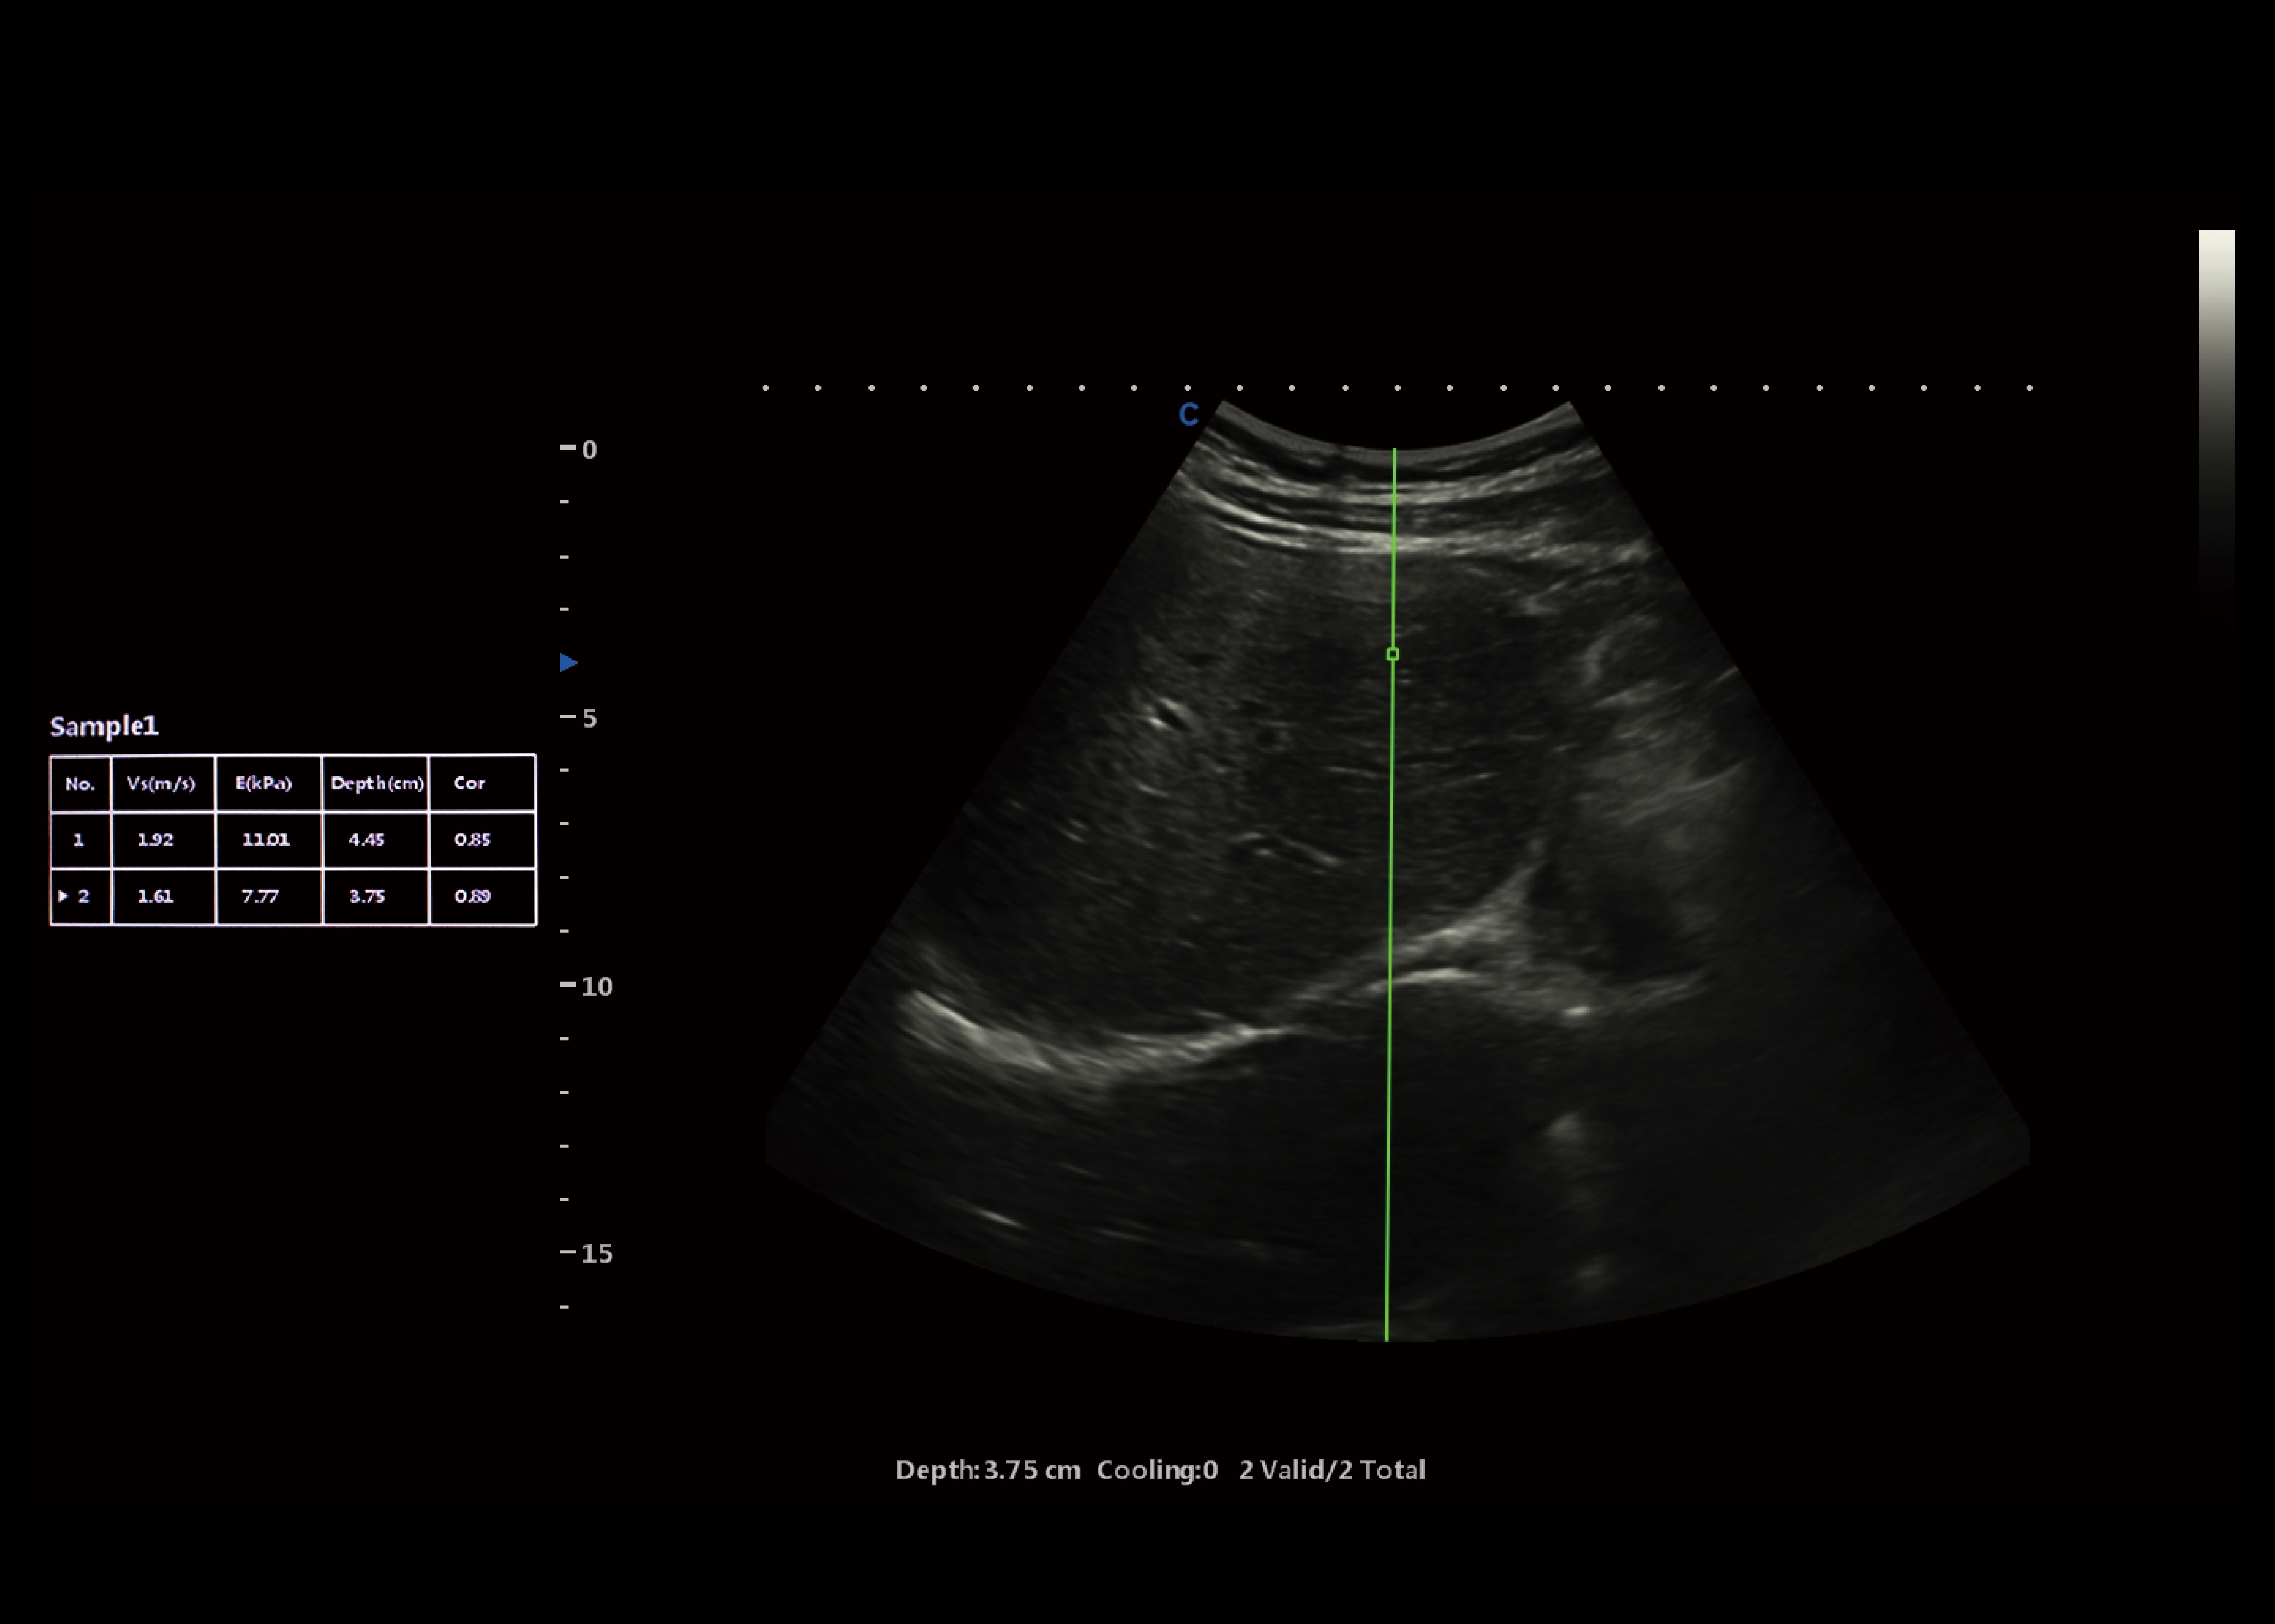

Scherwellen-Elastographie

● P-SWE Punkt-Scherwellen-Bildgebung, hochpräzise Einzelpunktmessung, höhere Penetration.

● 2D-SWE Surface Shear Wave Imaging, zweidimensionale Messung in Echtzeit, um mehr diagnostische Informationen zu erhalten.

● Das System kann eine Vielzahl von quantitativen Analyseparametern liefern, z. B. Geschwindigkeitswerte, Elastizitätsmodul und so weiter.